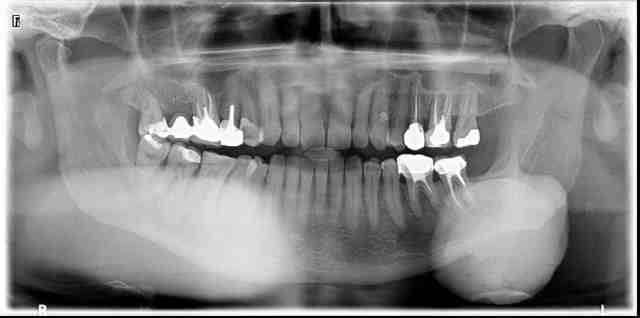

A votre avis, qu'est ce que c'est cette calcification sous le secteur 3 ?

A la palpation, tuméfaction très ferme. Indolore. Présente depuis 20 ans chez ce patient.

oui, palpation sous-mandibulaire. En intra-buccal : ras (sans palpation externe et sans radiographie, impossible de s'en douter).

Quand on regarde bien, à la jonction branche montante-branche horizontale, on a l'impression que c'est une excroissance osseuse. Mais bon...

Je dirai Calcification de la parotide, qui est descendue en raison de l'énorme poids du bazar !

On voit en partie haute, le début du canal, calcifié aussi.

C'est tout joli aussi sous 36/35

Mais alors, la grosse masse claire qui prend le secteur 4 en entier, c'est quoi ??

La projection de la structure qui est dans le secteur 3.

Une des séquelles est la calcification des ganglions cervicaux, faire un diag différentiel des calculs sub mandibulaires ou parotidiens.